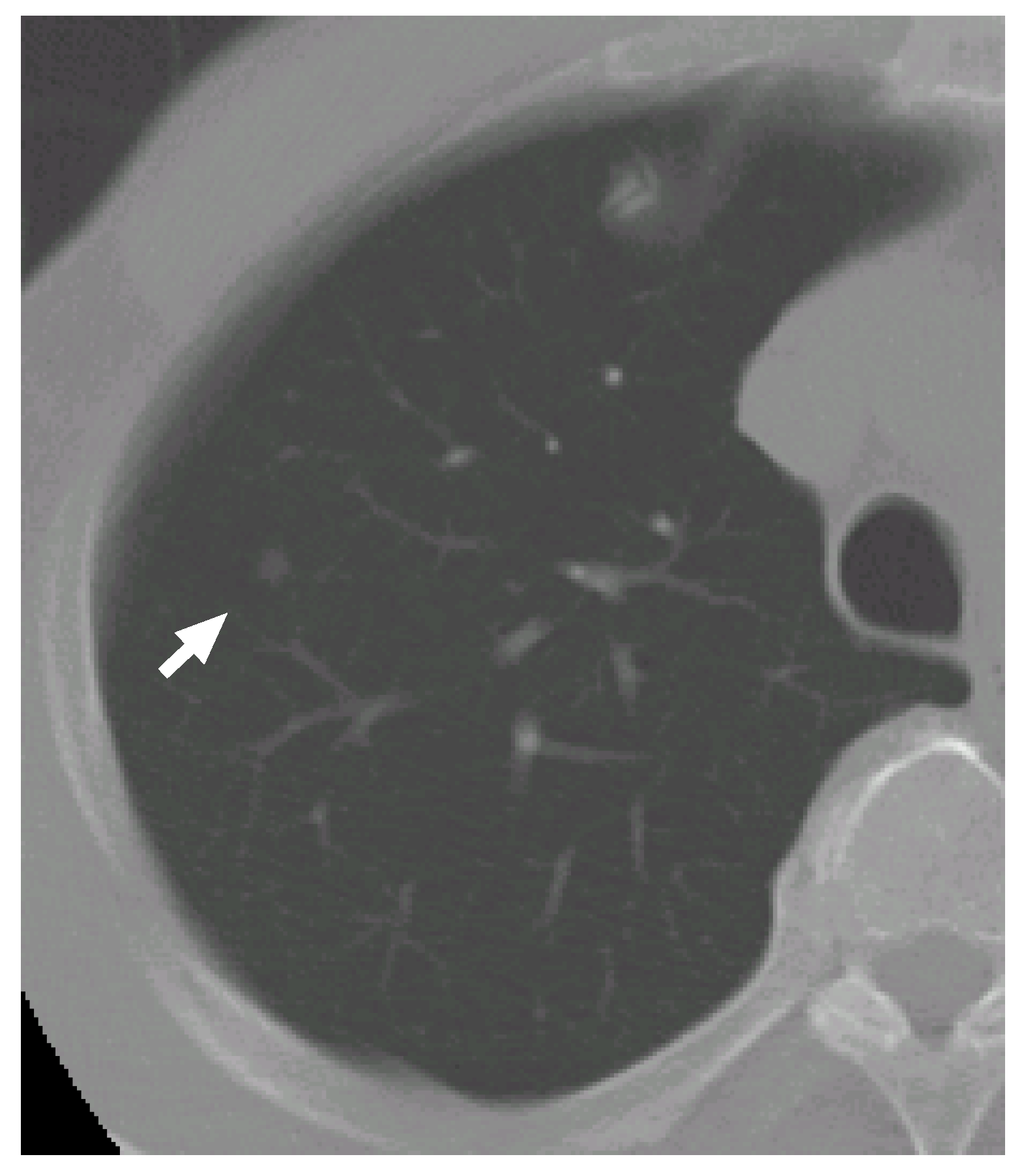

Figure 6 shows a slice cross section of a sample CT scan. The arrow indicates a nodule identified by a radiologist. The nodule is detected by our previous methods [8,27,28] as a nodule candidate. Figure 7 (a–c) shows a VOI of the nodule (Figure 7(b) shows the nodule). Figure 7(d–f) is template produced from the most likely nodule model that is depicted in Figure 8(a). They correspond to Figure 7(a–c), respectively. Figure 7(g–i) is produced from the most likely curved blood vessel model depicted in Figure 8(b), and Figure 7(j–l) is produced from the most likely bifurcated blood vessel model depicted in Figure 8(c). They correspond to Figure 7(a–c), respectively, in the same manner.

Figure 6. A slice cross section of a sample thoracic CT scan. The arrow indicates a nodule identified by a radiologist.

The posteriori probabilities of the most likely object models o N , o B c and o B b are 0.124, 0.087 and 0.100, respectively (the common constant values are omitted), and the ratio of the posteriori probabilities ρ 1 is 1.24. Because the ratio is larger than the threshold T ρ , the nodule candidate is correctly determined to be a nodule.

The nodule (Figure 7(a–c)) is faithfully reconstructed by the templates (Figure 7(d–f)). Although the nodule is shifted downward against the VOI (the nodule is not observed in the upper slice section shown in Figure 7(a)), the center of the nodule model is moved adequately. The nodule size is also estimated exactly. The diameters of the nodule and the nodule model are approximately 5.0 mm and 5.3 mm, respectively.

The effectiveness of Equation (3) can be seen in the templates of the curved and bifurcated blood vessel models shown in Figure 7(g–i) and (j–l), respectively. Because the nodule candidate is in the peripheral area of the lung region (see Figure 6 again), the mean radius of a blood vessel model μ r 1 B ( x B c ) becomes rather small, 0.89 mm, at this position. The small mean radius produces thin regions on the templates and the thin regions make the correlation coefficients low. Therefore, the probabilities of the blood vessel models become smaller than that of the nodule model.